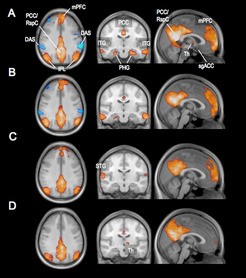

Netzwerk-Veränderungen über den Zeit­raum von 26 Minuten. Die Aus

Netzwerk-Veränderungen über den Zeit­raum von 26 Minuten. Die Ausdehnung des „Default Mode Netzwerkes“ (rot) und des gegenläufigen Netzwerkes (ACN, blau) in vier Stadien: A : Wachzustand, B : Schlafstadium 1, C : Schlafstadium 2, D : Tiefschlaf. Vor allem der mediale präfrontale Kortex [mPFC]) verliert seine Anbindung an das Netzwerk. Das Gegen-Netzwerk ist im Schlafstadium 1 schwächer, im Schlafstadium 2 dann nicht mehr nachweisbar.